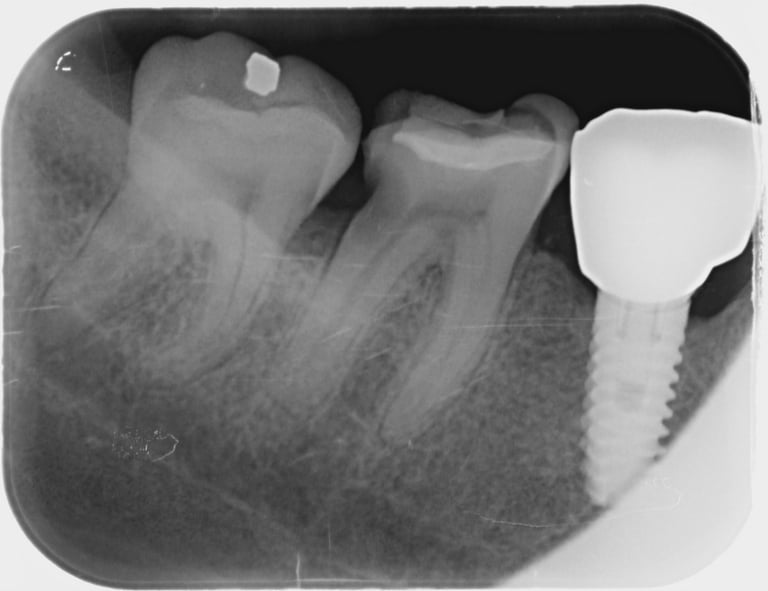

Con motivo de una revisión dental, se toman radiografías interproximales (de aleta de mordida) según sea necesario. Se toman 1 o 2 de cada lado de la boca. Si tiene caries muy activas , puede que sean necesarias radiografías interproximales con mayor frecuencia. Estas radiografías se toman para detectar caries en los espacios interdentales y para comprobar el nivel óseo.

En las radiografías interproximales se puede observar el inicio de las caries antes de que sean visibles en la boca. Por lo tanto, es posible iniciar un tratamiento preventivo antes de realizar un empaste. Las radiografías interproximales también permiten evaluar el nivel óseo alrededor de los dientes y, por consiguiente, indicar si existe periodontitis.